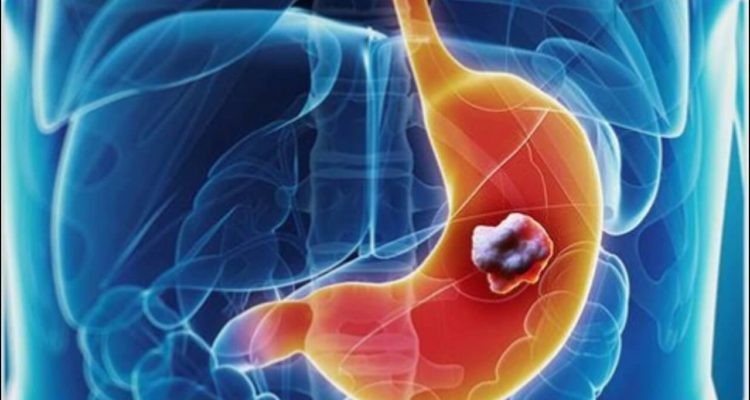

Фактори ризику та причини раку шлунка: генетика, ожиріння, куріння або спосіб життя?

Причина раку шлунка невідома, але є фактори ризику

Це фактор ризику номер 1. Однак близько чверті німців інфіковані цією бактерією, але тільки у частини з них розвивається рак шлунка. Чому вони хворіють, ще до кінця не з’ясовано, так само як і причини раку шлунка невідомі.

Хронічне запалення слизової оболонки шлунка і рефлюксна хвороба, в свою чергу, можуть збільшити ризик раку шлунка на стику з стравоходом. Також хвороба може розвинутися в результаті перенесених раніше операцій на шлунку.